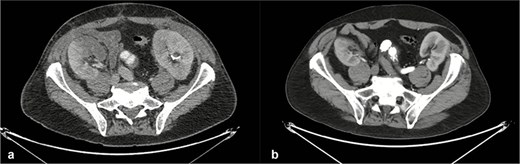

On admission, the patient was neurologically intact. Physical examination of the neck revealed a jugular venous pulse measuring 5 cm, with no carotid bruits. Both hemithoraces were well ventilated, and cardiac auscultation revealed regular rhythm with normal heart sounds and no gallops (S3 or S4). Abdominal examination demonstrated preserved peristalsis, a soft and non-distended abdomen, and a palpable, non-tender pulsatile mass in the mesogastrium. A systolic murmur graded IV/VI was auscultated over the mesogastric region. Peripheral vascular assessment revealed diminished distal pedal pulses with a capillary refill time of <2 s. A comprehensive imaging workup confirmed the presence of a complex aortoabdominal aneurysm involving both the suprarenal and infrarenal segments (Figs 1–3). Aneurysm dimensions are detailed in Table 1.

Contrast-enhanced thoraco-abdominal CT with dimensions of principal right renal artery (a), most superior left renal artery (b), most inferior left renal artery (c).